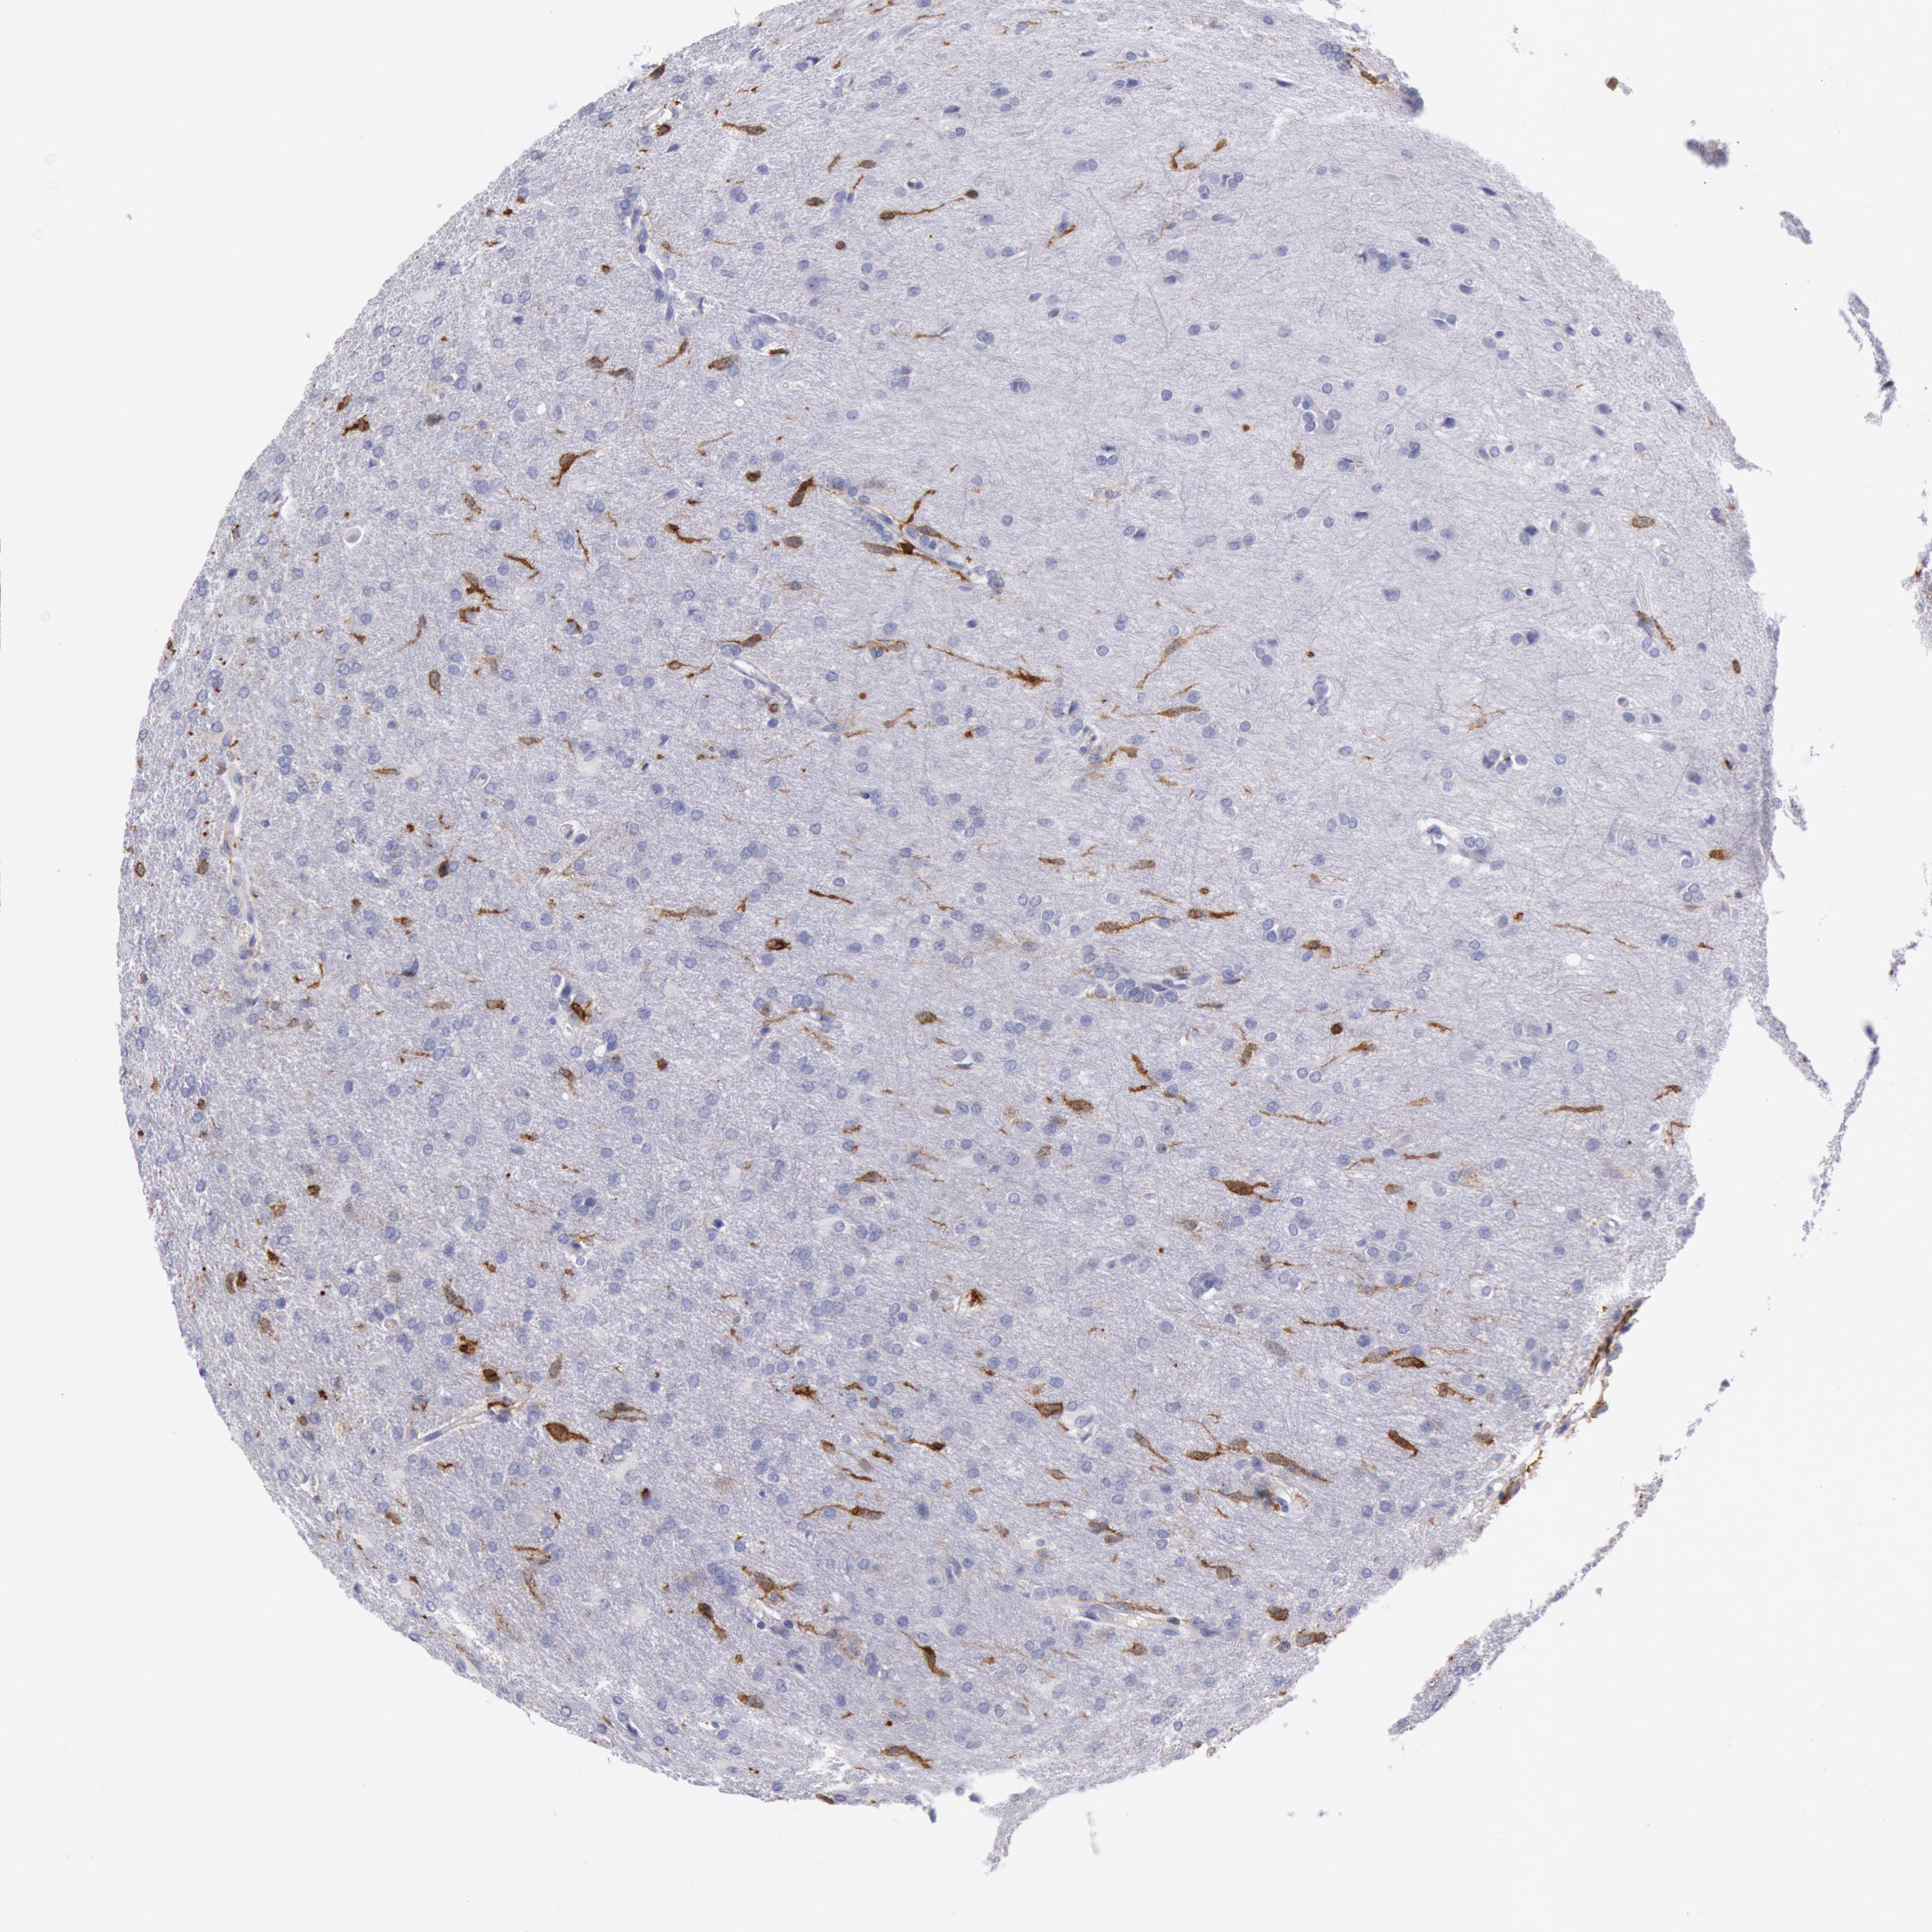

GLIOMA - Protein expressioni

A mouse-over function shows sample information and annotation data. Click on an image to view it in a full screen mode. Samples can be filtered based on level of antibody staining by selecting one or several of the following categories: high, medium, low and not detected. The assay and annotation is described here.

Note that samples used for immunohistochemistry by the Human Protein Atlas do not correspond to samples in the TCGA dataset.

Antibody stainingi

Antibody staining in the annotated cell types in the current human tissue is reported as not detected, low, medium, or high, based on conventional immunohistochemistry profiling in selected tissues. This score is based on the combination of the staining intensity and fraction of stained cells.

Each image is clickable and will lead to virtual microscopy that enables deeper exploration of all samples and also displays staining intensity scores, fraction scores and subcellular localization as well as patient and tissue information for each sample.

Glioma, malignant, High grade

Glioma, malignant, Low grade

Glioma, malignant, NOS